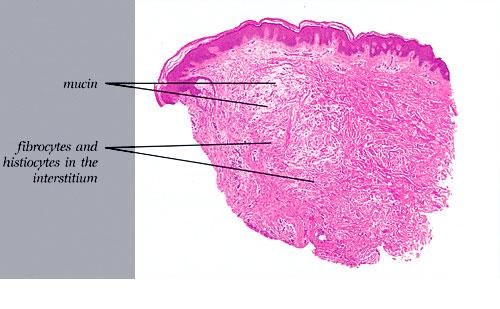

Regular demonstration of the presence of mucin in the dermis is possible only in pretibial myxedema, self-healing juvenile cutaneous mucinosis, and lichen myxedematosus. In reticular erythematous mucinosis, it is possible in most cases. In generalized myxedema, the amount of mucin usually is too small to be demonstrable, and in scleredema, mucin may be present only in the early stage.

The mucin found in these six diseases represents an increase in the mucin that is normally present in the ground substance of the dermis. It consists of proteins bound to hyaluronic acid (hyaluronan), which is an acid mucopolysaccharide or glycosaminoglycan. As a result of the great water-binding capacity of hyaluronic acid, dermal mucin contains a considerable amount of water. This water is largely removed during the process of dehydration of the specimen; consequently, in routine sections, the mucin, because of its marked shrinkage, appears largely as threads and granules.

The mucin present in the six types of mucinosis stains a light blue in sections stained with H&E. It also stains with colloidal iron. It is Alcian blue-positive at pH 2.5 but negative at pH 0.5 and shows metachromasia with toluidine blue at pH 7.0 and 4.0 but no metachromasia below pH 2.0 . It is PAS negative (indicating the absence of neutral mucopolysaccharides) and aldehyde fuchsin negative (indicating the absence of sulfated acid mucopolysaccharides). The mucin is completely removed on incubation of histologic sections with testicular hyaluronidase for 1 hour at 37″C .